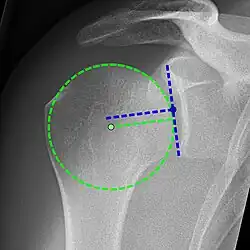

Projectional radiograph of normal glenohumeral position.[51]

X-ray projectional radiography cannot directly reveal tears of the rotator cuff, a 'soft tissue', and consequently, normal X-rays cannot exclude a damaged cuff. However, indirect evidence of pathology may be seen in instances where one or more of the tendons has undergone degenerative calcification (calcific tendinitis). The humeral head may migrate upward (high-riding humeral head) secondary to tears of the infraspinatus, or combined tears of the supraspinatus and infraspinatus.[51] The migration can be measured by the distance between:

• A line crossing the center of a line between the superior and inferior rims of the glenoid articular surface (blue in image).

• The center of a "best-fit" circle positioned over the humeral articular surface (green in image)

Normally, the former is positioned inferiorly to the latter, and a reversal therefore indicates a rotator cuff tear.[51] Prolonged contact between a high-riding humeral head and the acromion above it may lead to X-ray findings of wear on the humeral head and acromion; secondary degenerative arthritis of the glenohumeral joint (the ball and socket joint of the shoulder), called cuff arthropathy, may follow.[50] Incidental X-ray findings of bone spurs at the adjacent acromioclavicular joint may show a bone spur growing from the outer edge of the clavicle downward toward the rotator cuff. Spurs may also be seen on the underside of the acromion, once thought to cause direct fraying of the rotator cuff from contact friction, a concept currently regarded as controversial.